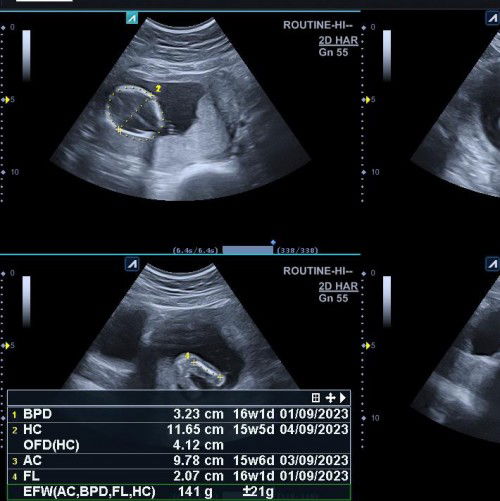

BB janin usia 16 week

Kemarin saya usg usia janin nya 16 week kata bu dokter ari2 nya menutup jalan lahir, terus Dd nya masih kuyus karena ps bagian wajah itu tirus banget sih emang. Pas di rumah Aku langsung down dan nangis sesenggukan. Kasian banget anakku. Emang usia 16 week berat 141gr tu kurus ya? Terus apakah plasenta/ari2 itu bahaya kalo letaknya disitu? Masih bisa geser ga ya. Bisa lahiran normal ga ya, bimbang banget :( Terima kasih bunda2 yg mau bantu jawab.